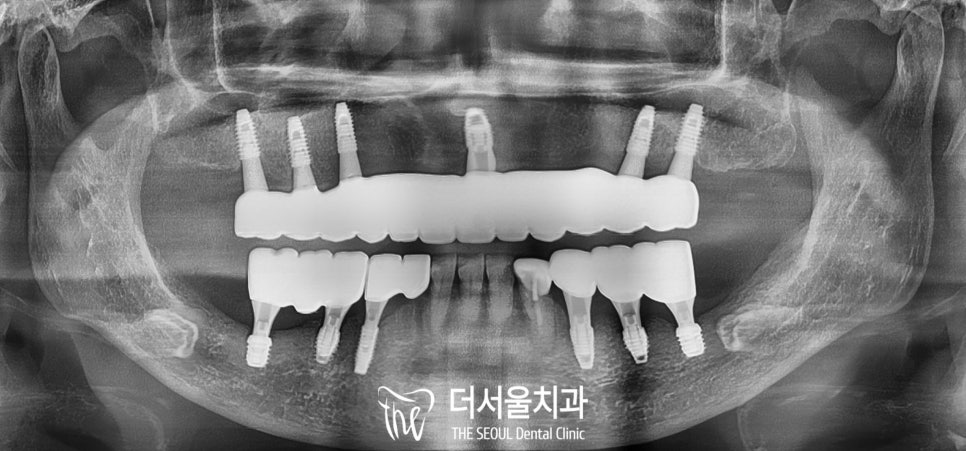

식립은 매우 성공적으로 끝났고

환자 역시 금연, 금주 같은

주의사항을 잘 지켜주셨기에

정말 만족스러운 결과가 나왔습니다.

디지털 풀아치는 성남 치과의원 에서

유지관리를 지속적으로 해드릴 수 있도록

교합면에 홀이 있는 SCRP type으로

만들어드렸으며

위아래 맞물리는데 불편함은 없는지도

여러 번 확인해 드렸습니다.

처음과 비교해 보면

드라마틱한 변화가 느껴지시죠?